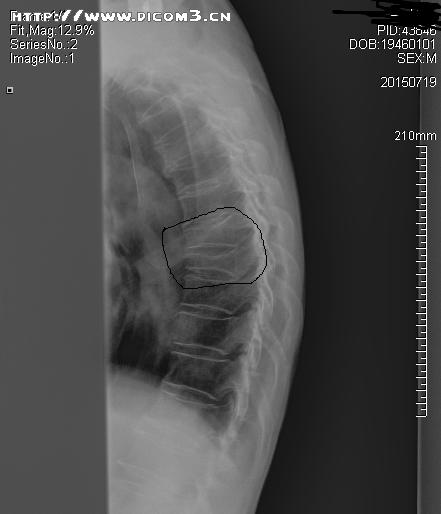

胸椎侧位片(标识处为压缩性骨折部位)

来诊时,患者已经12天未排大便,查体:腹部膨隆,脐上压痛,肠鸣音稍亢进,舌红苔黄厚腻,脉弦滑,见患者进诊室时就一直含胸驼背,追问患者病情,自述其后背部隐痛不适,不敢直腰,进一步扩大查体范围,查脊柱发现,胸8、9棘突尖、椎体两侧旁压痛叩击痛明显,建议患者行胸椎正侧位X片检查,患者满脸狐疑,“明明是肚子不好,拍什么胸椎片啊”,还好,之前攒了点人品,这时起了作用,患者虽然疑心重重,但最终还是听从了我的建议,拍片检查示:胸8.9压缩性骨折,再追问既往病史,患者无明显外伤史,但此前曾长期口服激素类药物,病情叙述到此打住,问题来了,患者好好的怎么就骨折了呢?即便有骨折,又与大便不通又有什么关系呢?